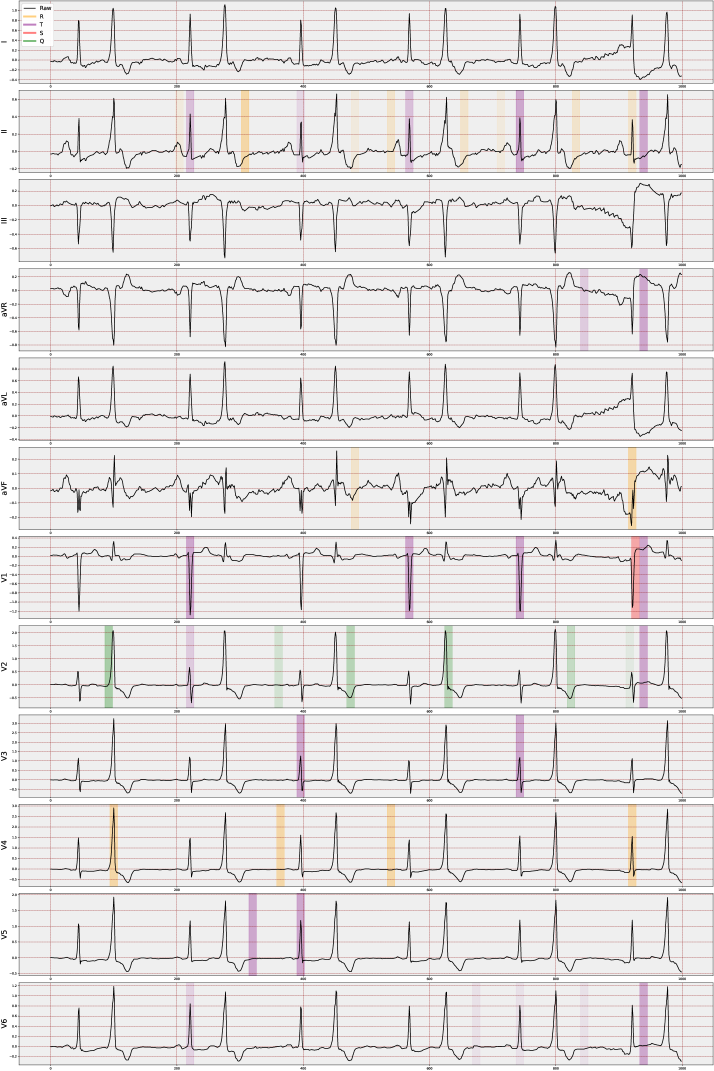

4.3 VCCE: Visualizing Counterfactual Clues on Electrocardiograms

We have developed a visualization method, VCCE, to enhance the presentation stage of the obtained counterfactual clues to the end-user, i.e., the clinician. This structure involves highlighting counterfactual clues obtained from the patient’s signal in the ECG report. For visualization, we offer various options that allow the display of peaks in chosen regions along with advanced features. These features are computed via amplitude differences and are presented as lines with their distance values overlaid on the ECG signal. Moreover, when visualizing counterfactuals, the more a specific feature is selected in an alternative world, the more it is strongly highlighted on the ECG report.

In essence, this approach, may adaptable independently of the ECG task, enables us to observe changes in PQRST across many “possible worlds," providing a means to perceive alterations across different scenarios. The main justification for assuming the applicability of VCCE across a wide range of ECG tasks is fundamentally rooted in the nature of the employed ECG features, similar to other ECG-dependent cardiac conditions. These features are extracted based on the structure of the P-, Q-, R-, S-, and T-waveforms (cardiac cycle) at a beat level, which remains a consistent term across all ECGs. The key advantage lies in the fact that these derived features offer distinct temporal and amplitude-level information that is inherently interpretable. Consequently, we can not only numerically analyze the generated counterfactual scenarios but also precisely determine their impact on specific waves within particular leads and beats.

In the proposed study, we note that the selected top 20 features are predominantly non-temporal due to their dependence on lead-wise amplitude characteristics across all MI cases in the dataset, with RR_Next being the only temporal one. Therefore, our visualization method primarily focuses on amplitude-based (non-temporal) features. Additionally, we have included four more features, selected by domain experts, to enhance individual resolution, such as distinguishing between inferior and anterior case differences. Consequently, we initiate a decoding process to unfold the temporally compressed beats. This decoding involves expanding the feature names to indicate the specific area influenced by the counterfactuals responsible for the change, encompassing details such as the lead, the waveform feature, and the beat associated with the counterfactual’s impact. This way, we are individually marking the features that contribute the most significant distinction between the two diagnoses.

5.3 Visualization of Counterfactual Clues

Understanding changes solely based on ECG features remains a time-consuming process within generated scenarios. Integrating simplified visualizations could effectively improve the grasp of pertinent indicators. To evaluate both the generated clues and the complete ECG report, we adopted custom measurement techniques. These measures involved assessments by expert cardiologists, incorporating both blind evaluations and interactive appraisals. This strategy improved the comprehensive evaluation of the generated clues.

In addition to the analysis in Section 5.2, our preliminary empirical investigations on visual assessments have led domain experts to conclude that the incorporation of four additional features (V2_T, V3_T, V4_T, and V6_T) can be both beneficial and necessary. These features have not only enhanced the quality of visualization but also improved the classification accuracy. This was evident in the identification of local MI cases, such as case ID 3234.0 in the dataset, where the system accurately identified 6 out of 7 individual beats, compared to the previous 2 out of 7.

51 reports were evaluated (Figure 5); 5 of them were excluded due to extreme artifacts (n=1, =0) and ventricular extrasystole (n=4, 10.25 ± 5.5). Of the remaining 46 reports, 17 were categorized as high (23.29 ± 1.04), 14 as moderate (20.28 ± 0.99), and 15 as low (11.20 ± 7.76) in terms of interpretability. The "±" symbol represents the mean and standard deviation of validation scores, respectively. A total of 31 reports were identified as acceptable.

The Figure C.2 illustrates the distribution of raw and denoised signals across various leads for a selected beat within the population. It is important to note that individual investigations might encounter significant noise, and this figure serves as an example to showcase the substantial variance in beats across the population. Moreover, the figure visibly demonstrates the considerable discrepancy in signal amplitude values between the NORM and MI populations.

The effect of denoising on one beat is demonstrated for two random samples in Figure C.3. Moreover, in Figure C.4, we can also observe how the signal in each lead changes discretely for the samples.